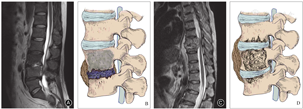

椎间盘被累及是支持化脓性脊柱炎的有力证据[10,11]。我们在手术过程中经常发现化脓性脊柱炎患者的椎间盘往往破坏严重,椎间隙充填着炎性坏死组织(图2A,B);而脊柱结核患者的椎间盘比较完整,可连同软骨终板一起整块切除(图2C,D,图3)。文献报道61%脊柱结核患者椎间盘得到保留,而化脓性感染患者的保留比例仅6%[9]。对椎间盘破坏程度的研究也显示,57.5%的结核患者椎间盘无破坏或仅轻度破坏;而化脓性感染患者中椎间盘完整者仅为3%[9]。对于化脓性脊柱炎破坏关节软骨,细菌释放蛋白水解酶可酶解破坏椎间盘和软骨终板;而结核杆菌由于缺乏蛋白水解酶,因此椎间盘可得到较好地保留[8]。

椎间隙狭窄程度也是鉴别诊断的有用信息(图2A,B)。化脓性脊柱炎患者由于椎间盘破坏,多在疾病早期出现椎间隙狭窄;而结核患者晚期才出现明显的椎间隙狭窄。Harada等[12]报告92.3%的化脓性脊柱炎患者出现椎间隙狭窄,而结核患者的比例为70%。